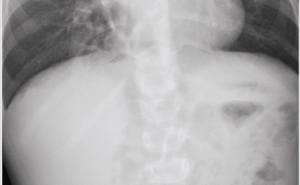

A previously healthy 4-year-old male, born late preterm by urgent cesarean delivery with an uncomplicated postnatal course, presents to the outpatient clinic for a chief complaint of worsening cough over the past 5 months. He denies current fever, rhinorrhea, shortness of breath, diarrhea, or vomiting. His cough has been worsening in severity and frequency, and mostly occurs during the daytime.